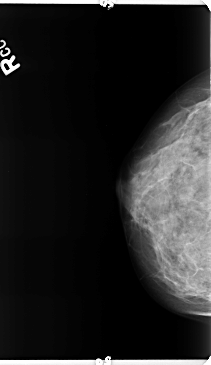

B_3359_1.LEFT_MLO

RIGHT_CC LINES 4736 PIXELS_PER_LINE 2736 BITS_PER_PIXEL 12 RESOLUTION 50 NON_OVERLAY

RIGHT_MLO LINES 4664 PIXELS_PER_LINE 2552 BITS_PER_PIXEL 12 RESOLUTION 50 NON_OVERLAY